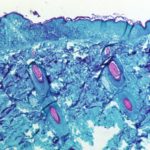

What is monkeypox? A microbiologist explains what’s known about this smallpox cousin

What is monkeypox? A microbiologist explains what’s known about this smallpox cousin Monkeypox causes lesions that resemble pus-filled blisters, which eventually scab over. CDC/Getty Images Rodney E. Rohde, Texas State University On May 18, 2022, Massachusetts health officials and the Centers for Disease Control and … [Read more...] about What is monkeypox? A microbiologist explains what’s known about this smallpox cousin